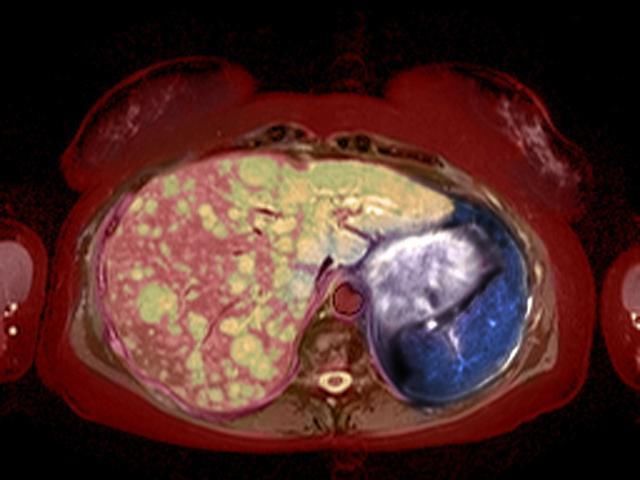

本以为临近毕业就能为自己的创业项目寻找到好公司,没想到,还没等来好公司的青睐,自己却先得到了病危通知——肝癌晚期。

多么可恶的玩笑,竟然开在了一个23岁的正在追梦的女孩身上,可是它真的发生了,小里的主治医生说,小里的肝癌发现得太晚了,癌细胞已经扩散开来,生命的时间正一天天的缩短。天,小里绝望到底,想想自己生来善良,不抽烟不喝酒,怎么就肝癌了呢。医生称,主要就是因为小里经常熬夜造成的。